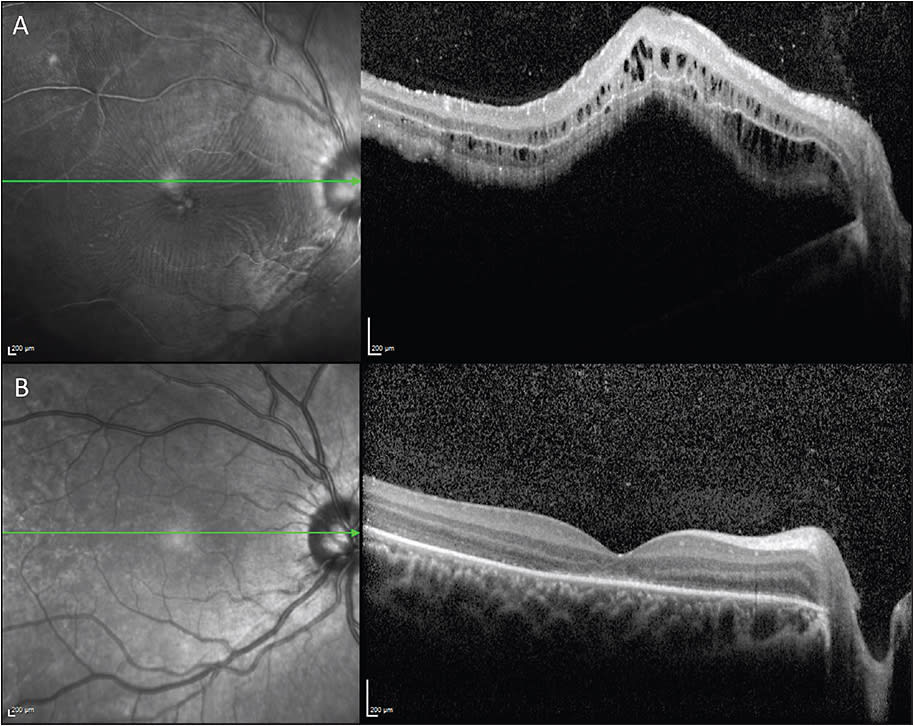

Scleral buckles, in conjunction with the creation of chorioretinal adhesions around retinal breaks with laser photocoagulation or cryotherapy, may be a favorable primary treatment option for rhegmatogenous retinal detachments in younger individuals. The fundus (Figures 4 and 5) and OCT (Figure 6) images illustrate a large inferior retinal tear and rhegmatogenous retinal detachment that resolved after treatment with a scleral buckle and cryotherapy. Successful treatment of rhegmatogenous retinal detachments with primary scleral buckling may reduce the risk of secondary cataract formation associated with vitrectomy.